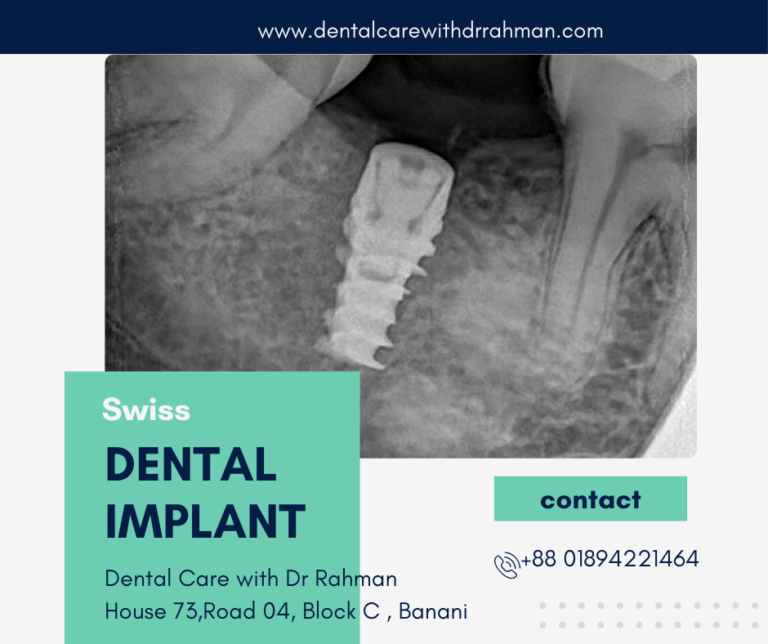

Application of modern technology

We have all the necessary advanced treatment : Digital dental X-Ray, CAD-CAM digital dental restoration , 3-D guided Dental Implant, patients. Moreover we 3D guided dental implant is new addition to dental implant treatment for accuracy of prothesis to ensure more success.

Now a days, 3D guided dental implant become most popular to place dental implant. Because of no surgical flap need to be reflect during surgery, reduce the surgery time and minimize post surgery risks.

3D Guided Dental Implant

3D Guide plan for Dental Implant -Single tooth Implant

What are the Main Benefits of Using Computer-Guided Implant Surgery?

- Precise and Accurate Dental Implant Placement

- Flap less and No incision

- Visualize vital anatomical structures allows better preserve during guided surgery.

- Detailed treatment planning beforehand helps to reduce or eliminate unexpected events during surgery.

- Time required for implant surgery can be substantially reduced

All-On-4 Guided Implant surgery at out clinic

Computer-guided surgery uses the images from the patient’s cone beam CT scan to precisely plan implant treatment. Guided surgery software allows us to visualize and manipulate images of the patient’s jawbone and the surrounding tissue, giving the opportunity to plan the most accurate approach to treatment.

All-on – 4 is more complicated dental implant procedure and need to be well planned and precise. Due age of the patients its sometimes difficult to bear lengthy surgical procedure. Planning with #D Guide minimize the operation time and reduce post operative complications.